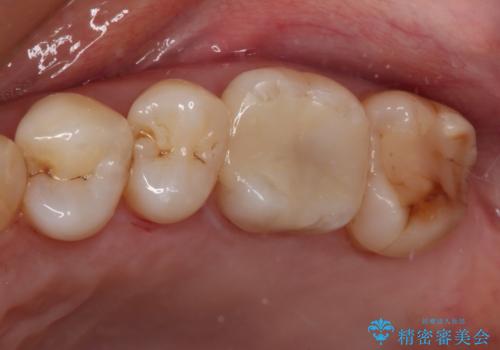

放置した虫歯 根管治療とオールセラミッククラウン